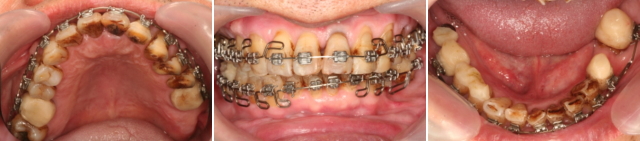

この患者さんのように、噛み合わせが病気の原因となっている場合は、矯正によって歯を移動させ、新しい噛み合わせを作ることも必要となる場合があります。矯正治療は、装置がお口に入ったり、期間・費用のデメリットもありますが、治療後の長期安定が得られるメリットは大きいです。治療期間が長くならないようにしています。この患者さんは1年で矯正治療は終わりました。